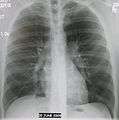

- Normal AP CXR

Normal lateral CXR